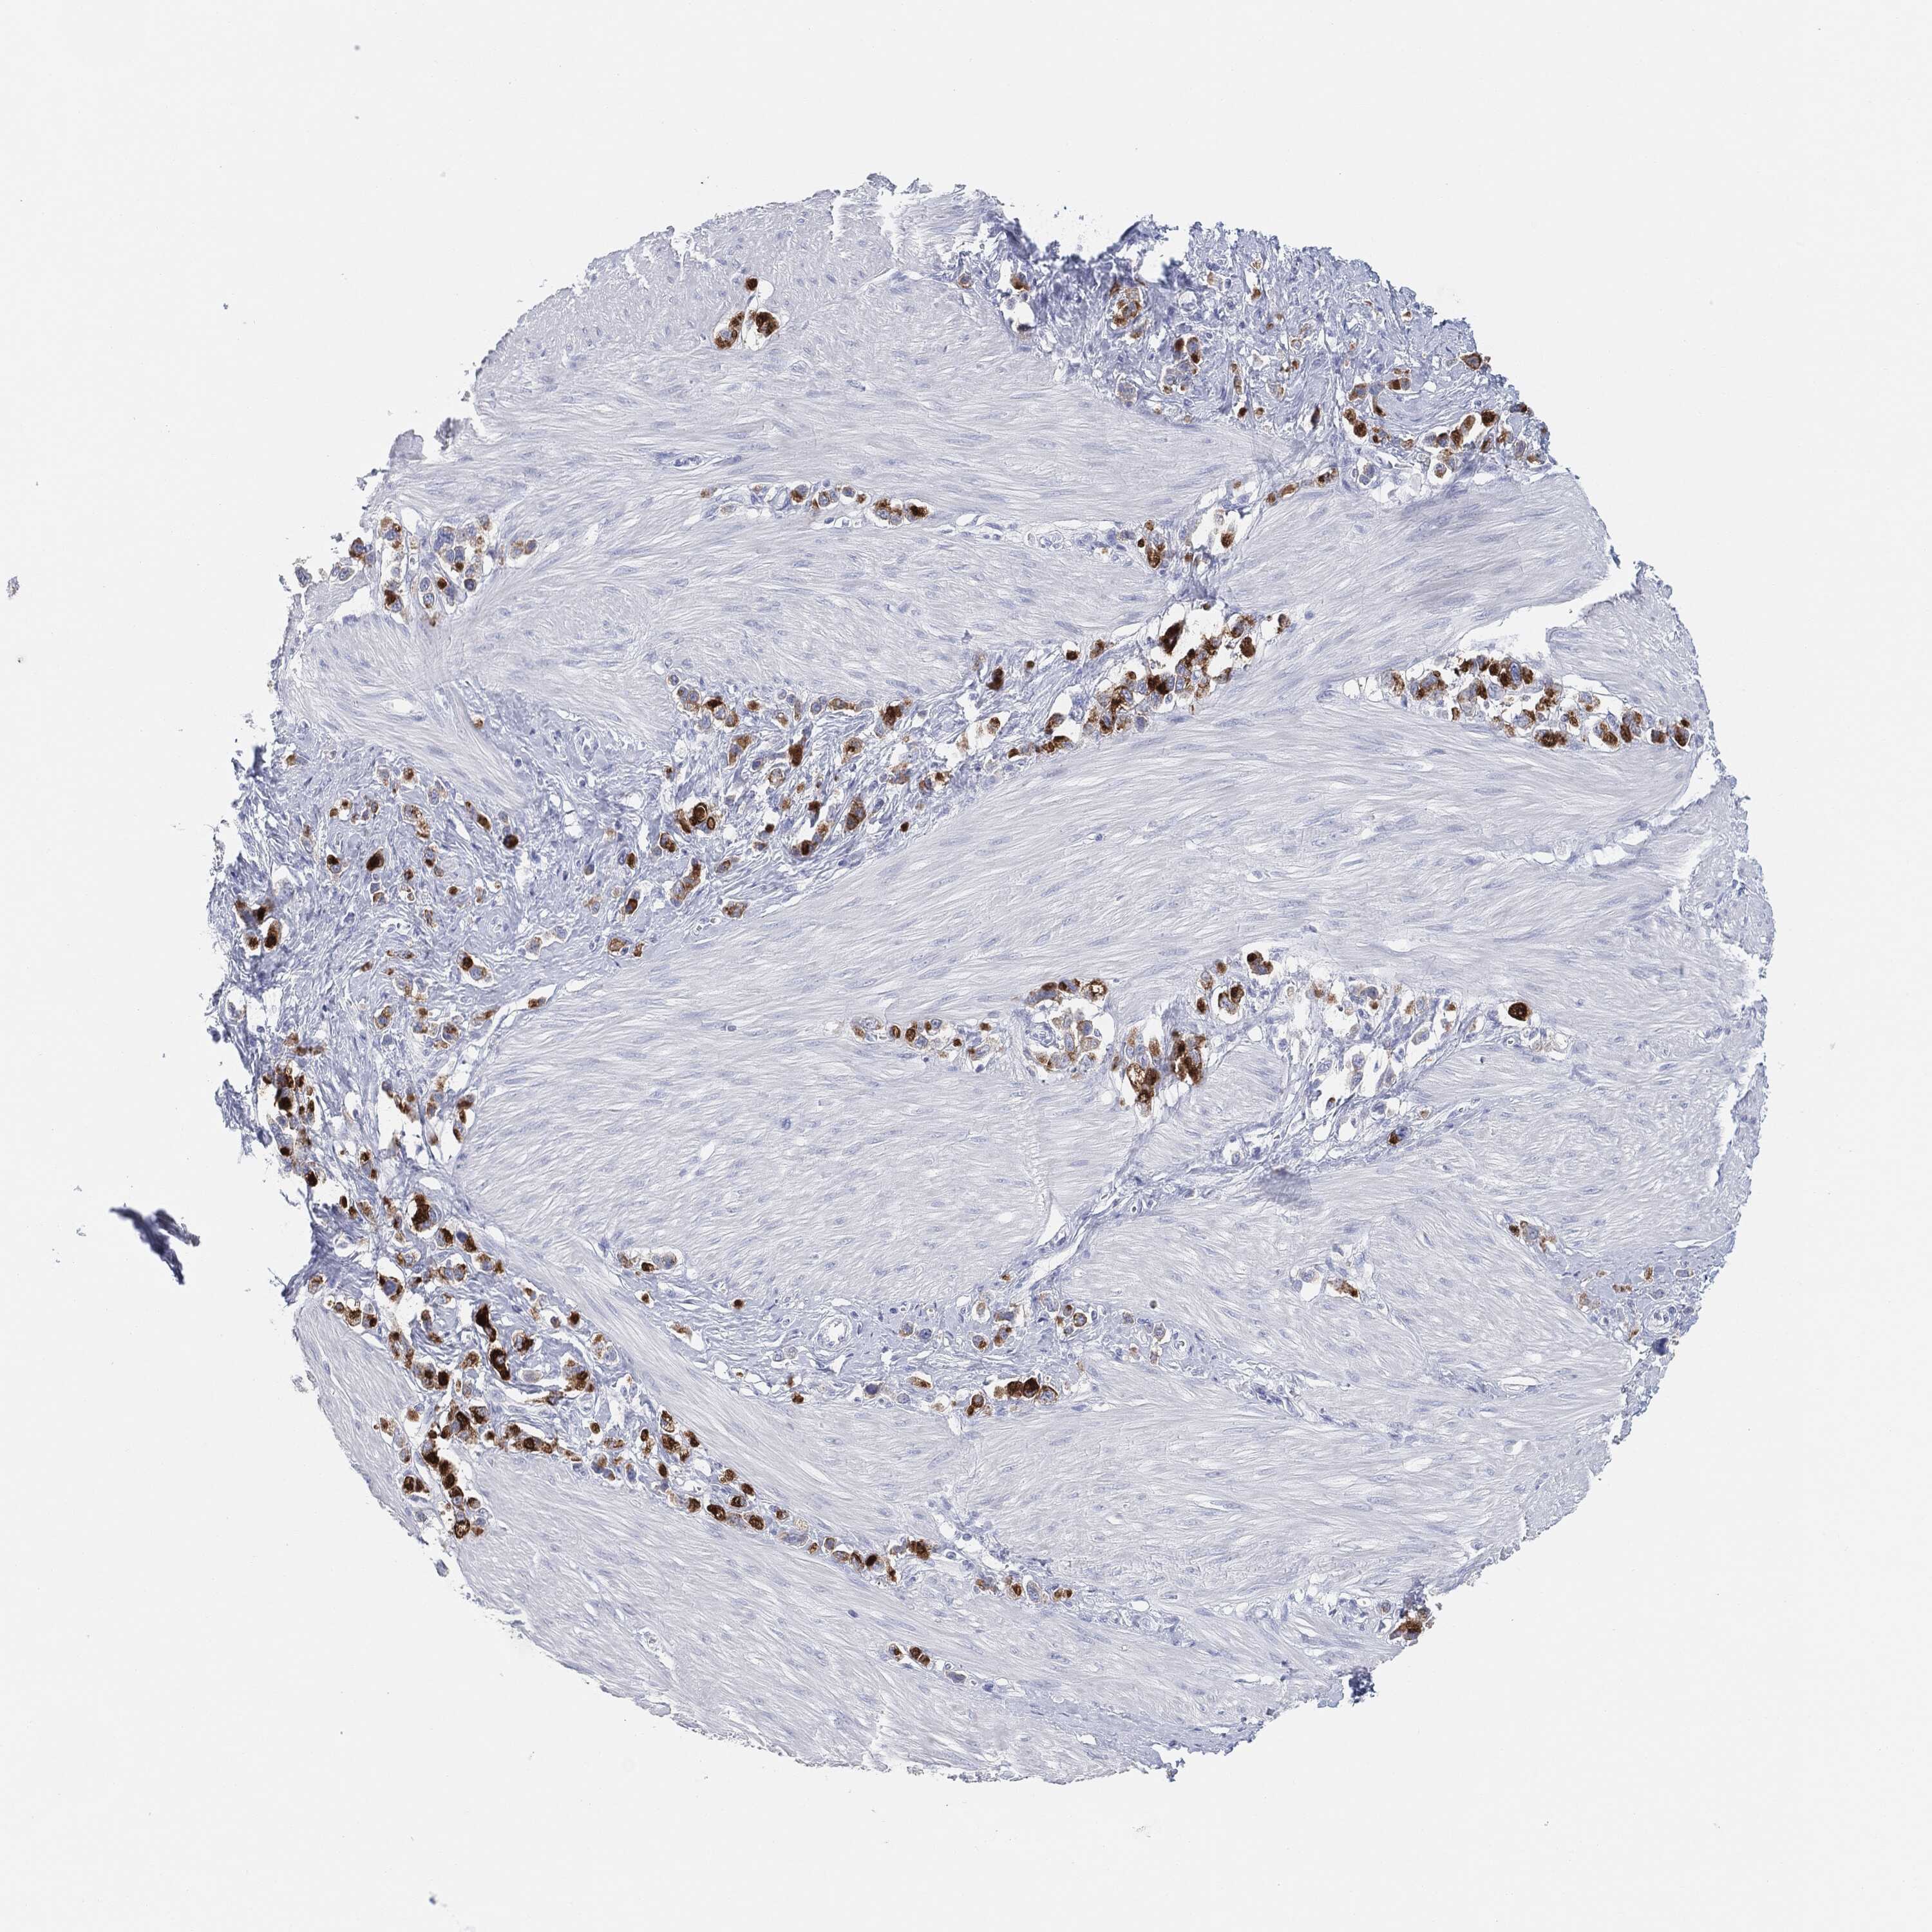

STOMACH CANCER - Protein expressioni

A mouse-over function shows sample information and annotation data. Click on an image to view it in a full screen mode. Samples can be filtered based on level of antibody staining by selecting one or several of the following categories: high, medium, low and not detected. The assay and annotation is described here.

Note that samples used for immunohistochemistry by the Human Protein Atlas do not correspond to samples in the TCGA dataset.

Antibody stainingi

Antibody staining in the annotated cell types in the current human tissue is reported as not detected, low, medium, or high, based on conventional immunohistochemistry profiling in selected tissues. This score is based on the combination of the staining intensity and fraction of stained cells.

Each image is clickable and will lead to virtual microscopy that enables deeper exploration of all samples and also displays staining intensity scores, fraction scores and subcellular localization as well as patient and tissue information for each sample.

Antibody HPA031634

Antibody CAB080501

Antibody CAB080502

Antibody CAB080503

Staining

High

Medium

Low

Not detected

Intensity

Strong

Moderate

Weak

Negative

Quantity

>75%

75%-25%

<25%

None

Location

Nuclear

Cytoplasmic/membranous

Cytoplasmic/membranous,nuclear

Adenocarcinoma, NOS

Adenocarcinoma, High grade